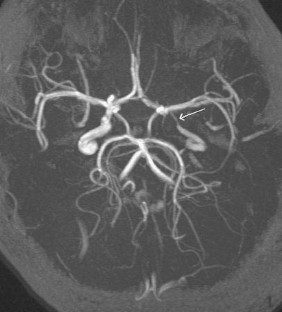

Mucocele of the sphenoid sinus

The sphenoid sinus is the least common site of mucocele of all paranasal sinuses. It is very rare in children, especially in those younger than 12 years when pneumatization of the sphenoid sinus is completed. We report a case of histologically proven sphenoidal mucocele in a 5-year-old child. The child presented with an acute onset of significant visual impairment and headache. His vision gradually improved after trans-nasal sphenoidotomy and drainage of the sinus content with return of complete normal baseline vision after 2 months.

Fig. 2